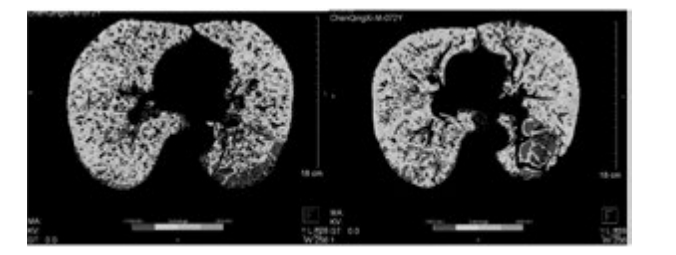

從表3、表4提示,CT 值在-1000 至-951 比例有所下降,Class4( % ) 亦明顯下降,故肺氣腫較治療前好轉(zhuǎn)。

例1患者行干細(xì)胞移植前后肺部 CT 檢查

下圖為雙源CT肺實(shí)質(zhì)分析軟件,深藍(lán)色表示CT值在-1000 至-951,治療后較治療前深藍(lán)色面積明顯縮小。

雙源CT肺實(shí)質(zhì)分析軟件